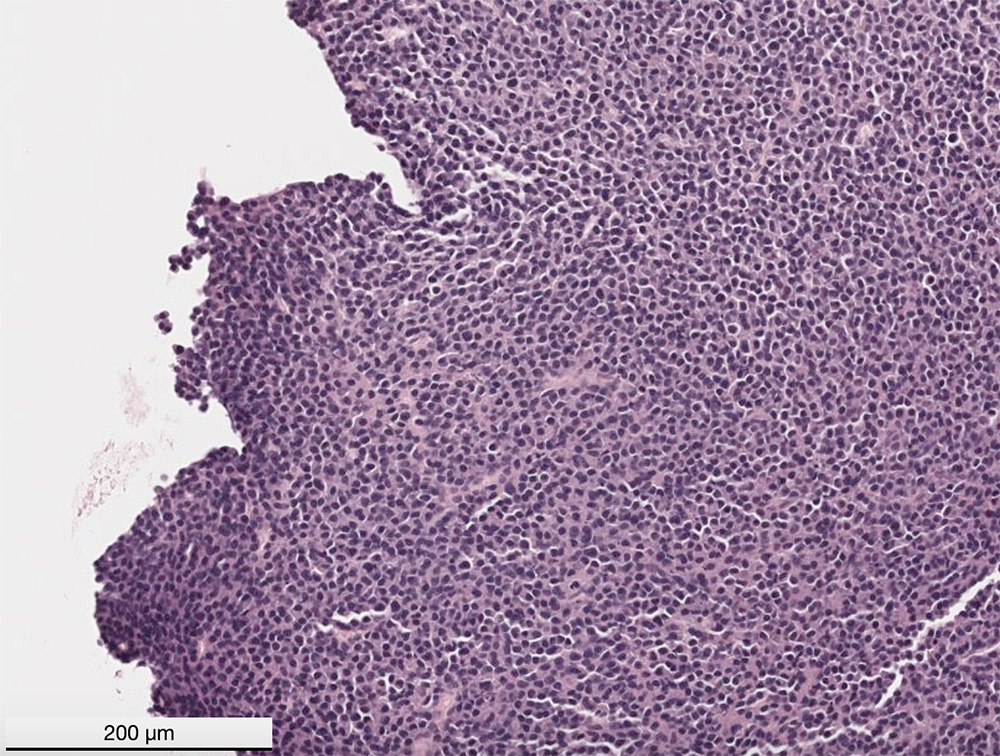

This captured image of the digitized slide of a cryostat section of the mass revealed sheets of round cells supported by fine stroma. The cells extended to the cut margins and infiltrated muscle and bone marrow (not shown). The cells had eccentric nuclei with stippled to clumped chromatin and no nucleoli. They had a moderate amount of amphophilic cytoplasm with a perinuclear clear zone, which are features compatible with plasma cells (H&E stain).